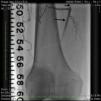

Case reportA 50-year-old Caucasian woman with hypertension, tobacco abuse, and peripheral arterial disease with life-limiting claudication had stents placed in bilateral 80% ostial iliac artery lesions two months previously. She was also noted to have a CTO of the left SFA at the ostium with no obvious stump (Figure 1) which was reconstituting distally via collaterals just above the popliteal artery (Figures 2 and 3). Due to her ongoing symptoms despite optimal medical therapy, it was decided to intervene on the SFA. Since there was no obvious stump of the occluded SFA proximally, we decided to approach the CTO through a retrograde approach.